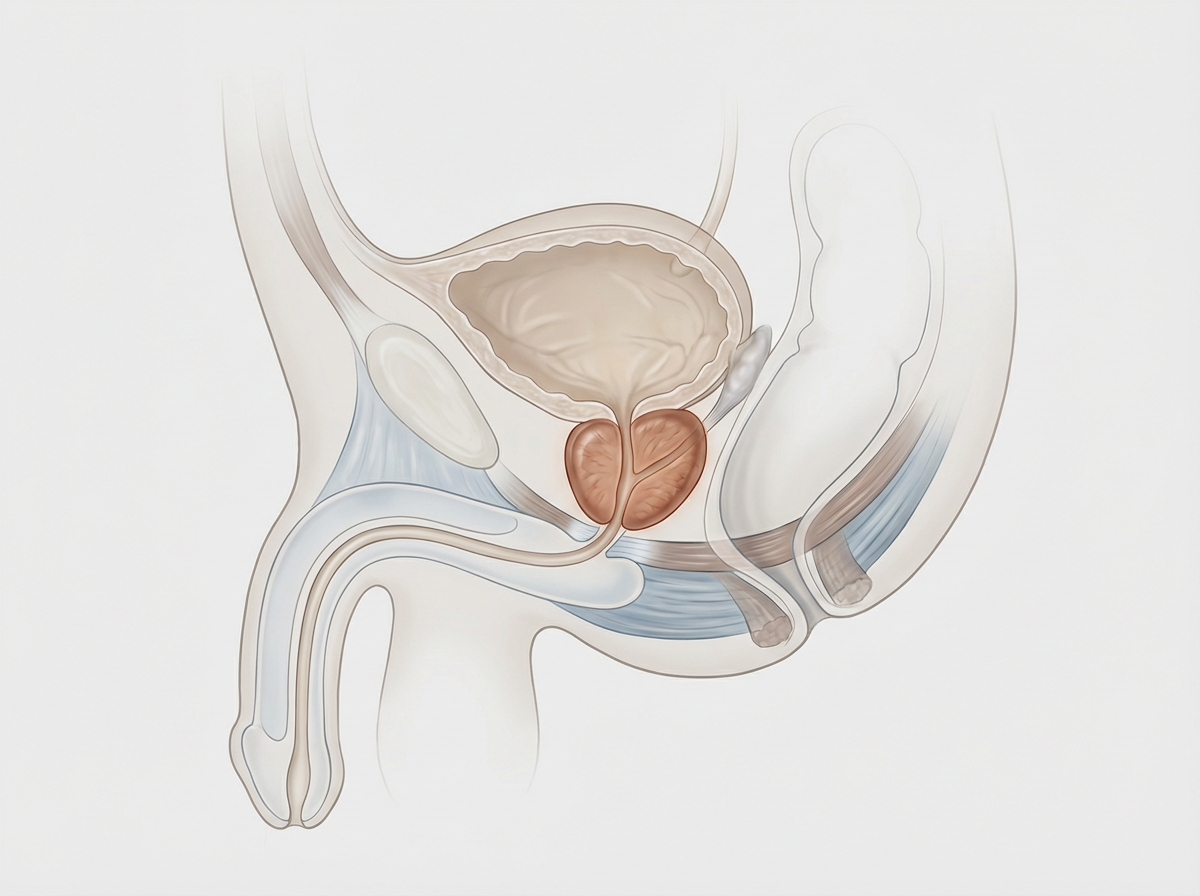

Enucleazione laser a fibra di tulio della prostata (ThuFLEP). Tecnica avanzata e mininvasiva per il trattamento dell’ipertrofia prostatica benigna, che consente la rimozione precisa del tessuto in eccesso con minimo sanguinamento. Recupero più rapido, maggiore sicurezza e miglioramento significativo dei sintomi urinari, per una migliore qualità della vita.

Hai problemi ad urinare a causa dell’ingrossamento della prostata? Presso la clinica Fabjan in Slovenia eseguiamo l’enucleazione laser della prostata con il laser a fibra di Thulium – ThuFLEP.